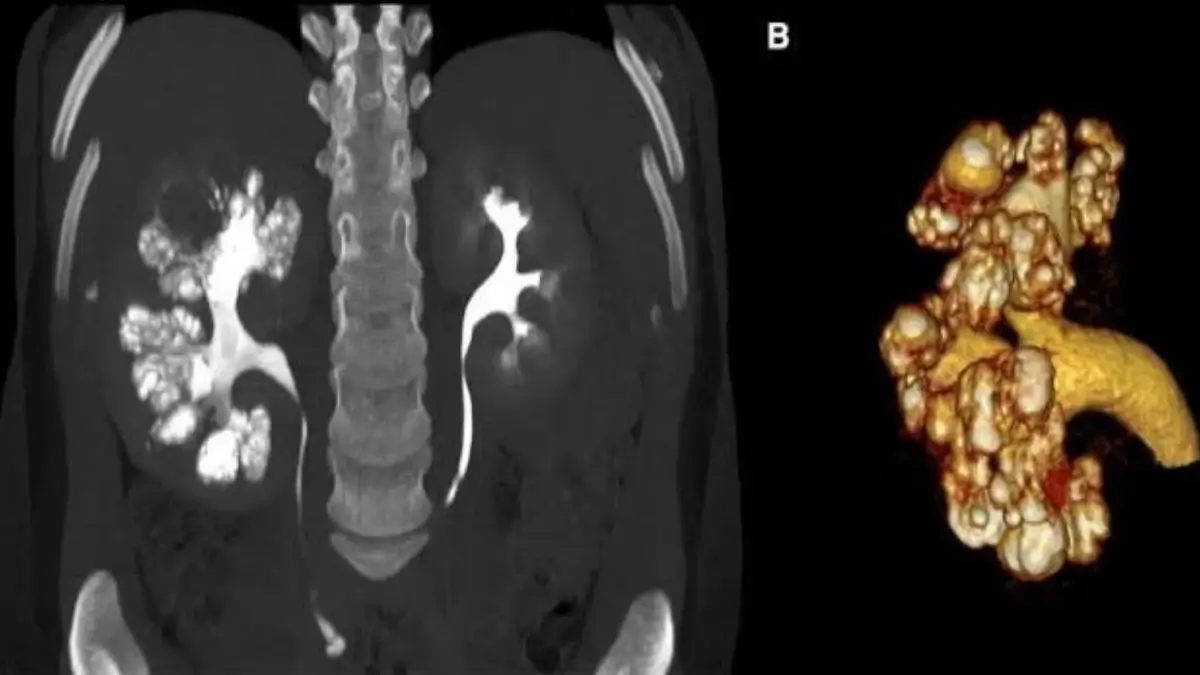

কিডনির দু’টি অংশ থাকে। একটিকে বলে কর্টেক্স এবং অপরটি মেডুলা। কিডনির মেডুলা অংশে কোনো কারণে সিস্ট তৈরি হলে তা দেখতে অনেকটা স্পঞ্জের মতো লাগে এবং এই কারণে এটিকে মেডুলারি স্পঞ্জ কিডনি বলে।

Medullary Sponge Kidney নির্ণয়ের জন্য ভালোভাবে রোগীর ইতিহাস জানতে হবে। পরিবারের কারোর এই রোগ আছে কি না তা প্রথমেই ভালোভাবে জেনে নেওয়া উচিত। তবে সঠিকভাবে রোগ নির্ণয়ের জন্য রোগীর ইতিহাস জানার পাশাপাশি প্রয়োজনীয় পরীক্ষা নীরিক্ষার কোনো বিকল্প নেই। যেসব পরীক্ষার মাধ্যমে রোগটি সনাক্ত করা সম্ভব হয় সেগুলো হলো আইভিইউ, আল্ট্রাসনোগ্রাম, সিটিস্ক্যান, ইত্যাদি।